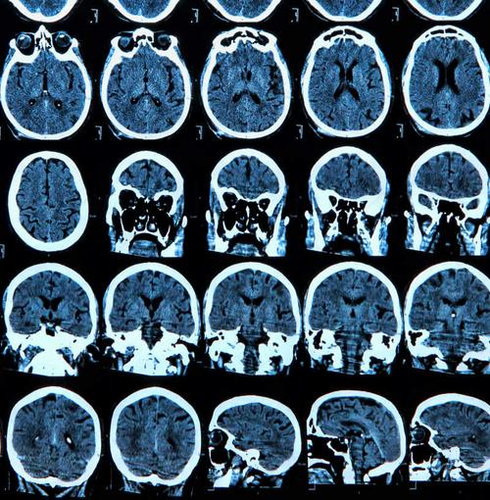

x光片特别适合用于骨骼和胸部疾病的检查,但是由于x光在检查过程中容易受到深浅组织的影像相互重叠和隐藏的影响,有时需要多次不同角度来拍摄,才能看的清楚进行诊断,而mri对中枢神经系统(脑和脊髓)、血管、肌肉及软组织等方面疾病有较全面的诊断作用。